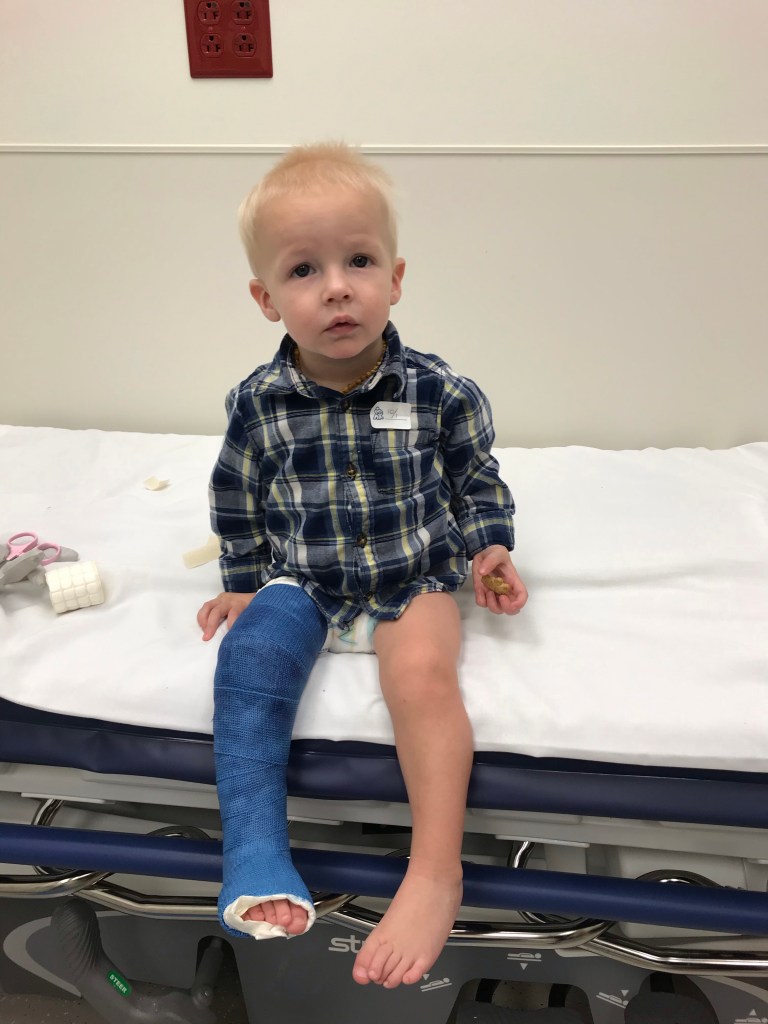

In the middle of all of our mess, Emery was put into a full leg cast to finish straightening out his foot. He spent two weeks in the first cast and another two weeks in a second one. They didn’t slow him down much at all but they did make him VERY cranky.